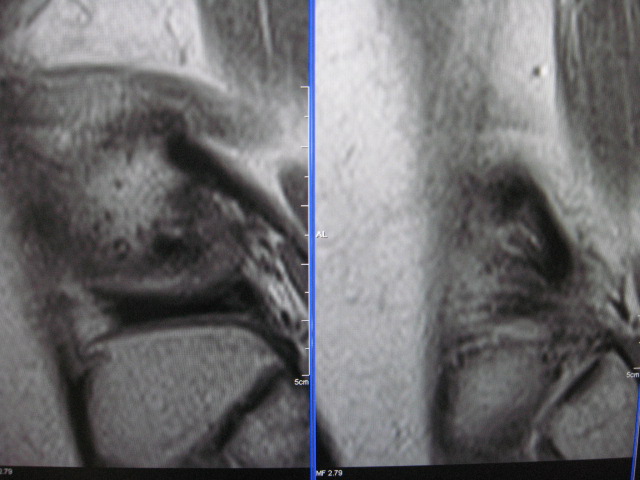

以下是引用克山在2007-10-21 9:57:00的发言:[br]符合股骨外侧髁剥脱性骨软骨炎。创伤是其主要原因,病理上为软骨下骨质局限性缺血性坏死,好发股骨内外侧髁,mr表现为软骨下局限性长t1长t2信号,有时t2像周围可见条状高信号。

以下是引用453506471在2007-10-19 22:23:00的发言:[br]剥脱性骨软骨炎